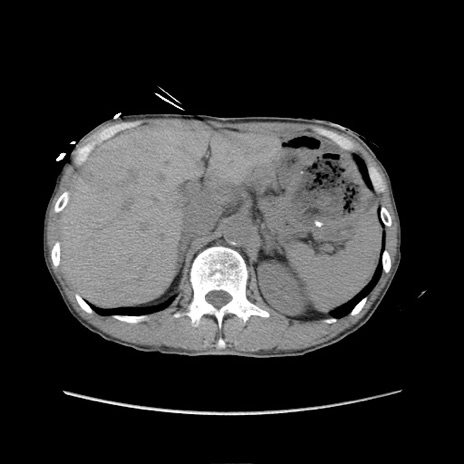

症例11(横断像)

【症例】 60歳代男性

【主訴】 下腹部痛

【現病歴】 本日夜中より下腹部痛の症状認め、受診。

【既往歴】 膀胱癌(膀胱全摘+尿管皮膚瘻術) 、胃癌術後

【身体所見】 BT 35.3℃、PR 58/min、BP 136/98mHg、腹部平坦、軟、腸蠕動音±、ストマ留置あり、左上腹部~正中部に圧痛あり、反跳痛なし。

【データ】WBC 5100、CRP0.01